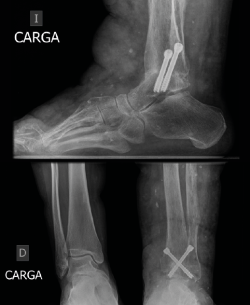

A los 6 meses se obtuvieron signos radiográficos de consolidación completa de la artrodesis (Figura 5). La paciente refirió una resolución completa del dolor y mejoría de la capacidad para la deambulación a los 6 meses, que se mantuvo en los siguientes controles.

Figura 5. Control radiográfico a los 6 meses donde se observa una consolidación completa con paso de trabéculas y clínicamente deambulación sin dolor por parte de la paciente.